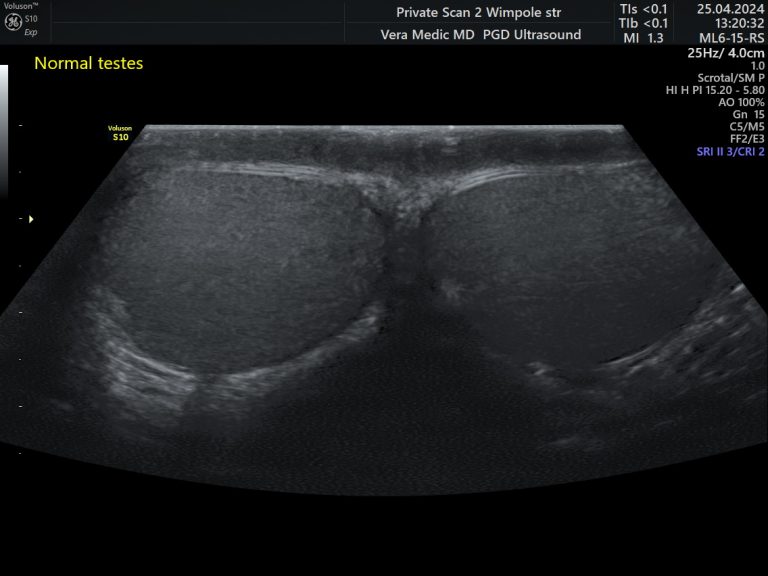

A testicular ultrasound examination, sometimes called a scrotal ultrasound or groin ultrasound scan, is a simple, safe, and pain-free imaging procedure used to assess the male reproductive system. It uses sound waves to produce detailed images of the testicles and the surrounding structures within the scrotum.

A testicular ultrasound scan is quick, accurate, and does not involve radiation, making it a trusted and effective diagnostic tool for men of all ages.

Testicular ultrasound scan is entirely safe and painless procedure, which uses high-frequency inaudible sound waves to obtain the insight and the images of the testicles and scrotum area.

Ultrasound probe will gently glide over the area while the client is placed in a comfortable reclining position. A small amount of ultrasound gel is applied to the area and the ultrasound probe then gently glides over it, scanning and recording the images, while the Doctor talks through their findings and explains what is being seen on the big screen.

The ultrasound scan will throughly examine the testicles and the surrounding tissue of the scrotum (the skin pouch that holds the testicles) for any abnormalities.